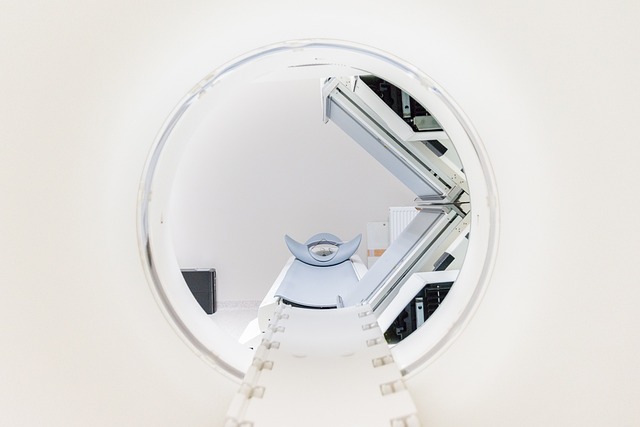

2. 개방형 MRI (Open MRI) 활용

개방형MRI는 기존 폐쇄형MRI와 달리 측면이 열려있어 공간확보가 가능합니다.

특징:

- 측면 개방으로 압박감 감소

- 보호자나 의료진과 소통 가능

- 검사시간 약간 증가할 수 있음

- 영상품질은 최신 기술로 우수함